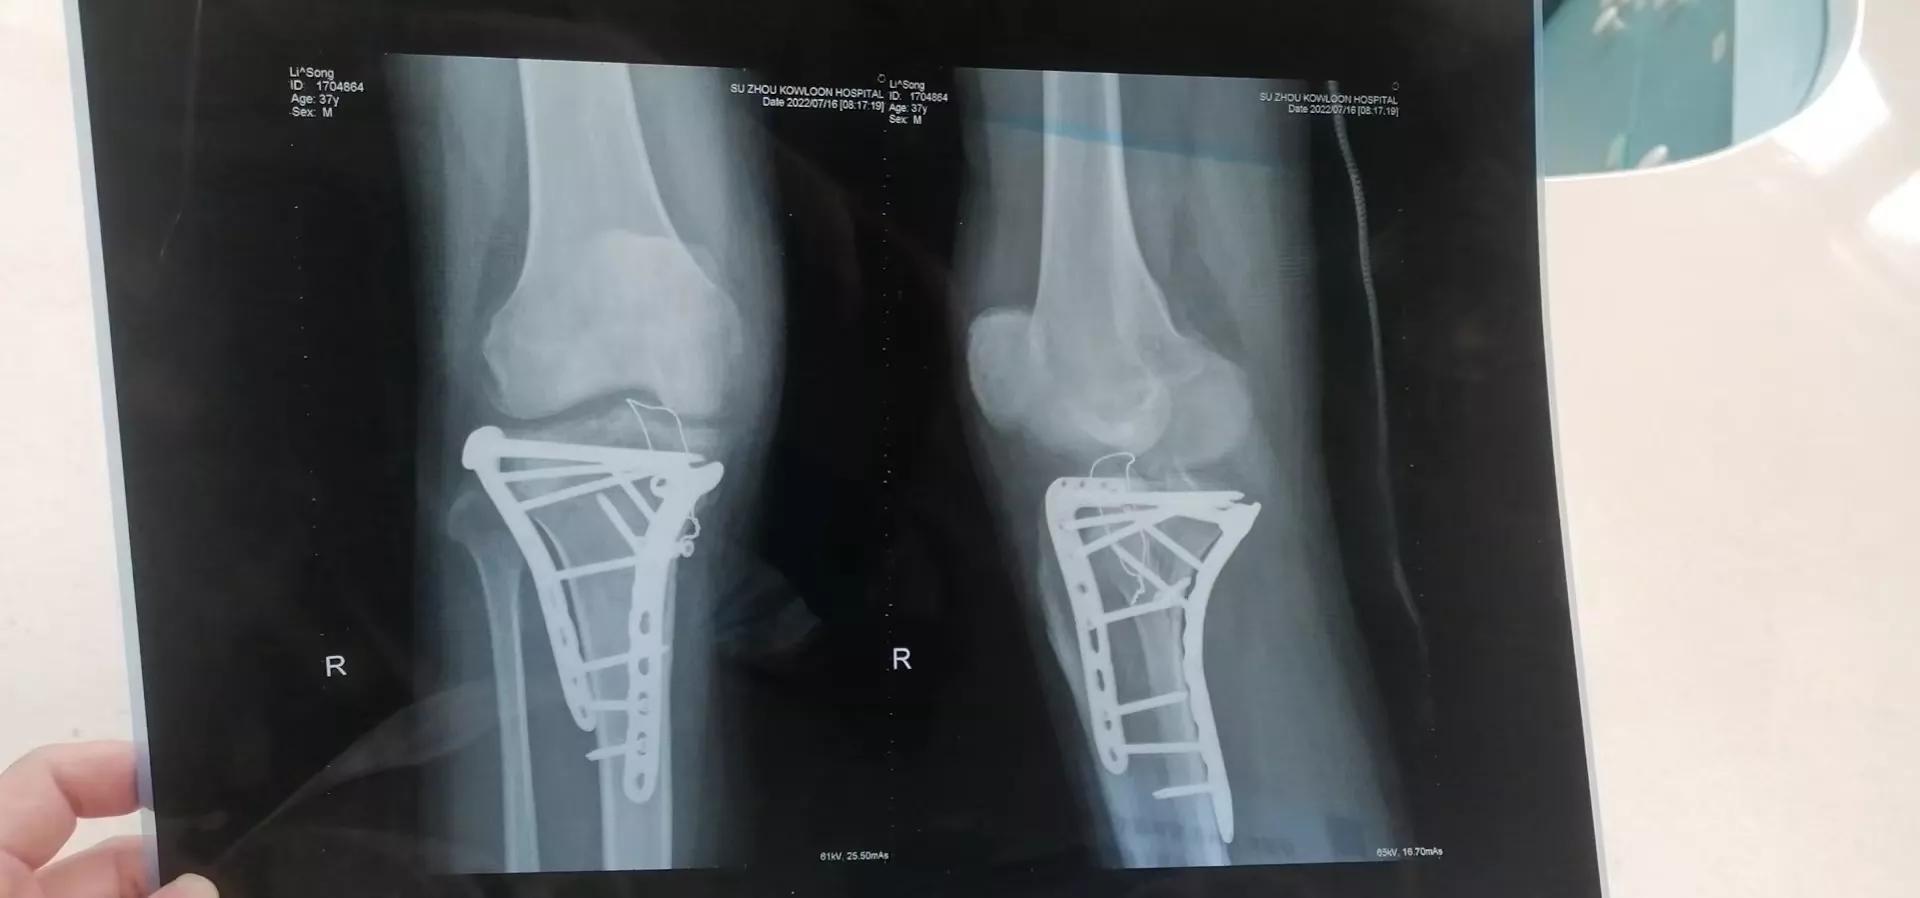

大家都知道我是在5月26号骨折的,后来做的手术,术后是在6月4号出的院,当时医生就有所嘱托要落地运动,不要负重,所以我回家后的一个礼拜后就开始落地行走了,没有任何问题,家里人对我也是很照顾,所以恢复进展的很好,中间虽然出现很多生活上的问题,但是我在条友们热心建议下还是处理的不错,在这里感谢条友们的衷心建议,让我能很快从郁闷无助到对生活慢慢充满信心,也让我看清楚的生活他就那个样子,你都需要认真的对待,不管它怎么弄你,就像一句台词一样,生活百般滋味,我们还需笑声面对。其实回头想想这一个半月的时间虽有争吵,就是一些工作上和生活上的琐事,过程中我打赢了一场官司,讨回来了5万块钱,之前有个朋友借我5万块钱,后来用各种理由推脱不给,这样就拖拖拉拉的持续了5年,后来我出了车祸,我老婆硬是打官司收集证据,打赢了,这也对我们的生活增添了一些生机,话锋一转我们回到骨折上来,就在上周六,我们去了我家附近的苏州九龙医院,做手术不是在这家做的,是在苏州瑞华骨科医院做的,我本以为九龙的医生会告诉我们后续的康复计划和要不要丢掉石膏,但是当我拿着片子和报告给他的时候,一脸不情愿,说你们在哪做的手术就去哪里问情况,我这不发表意见,唉,没办法就是不说骨折怎么样了的话题,后来在我们的苦口婆心下他简单说了几句,从片子看康复的还行,可以考虑丢掉石膏了,所以我们就这样出来了。昨天我发头条文章,有很多条友建议我现在就丢掉石膏,@郜玥家长505@幽落0915@幽落0915 @zhx19811010特别感谢这几个条友,通过跟他们不断的互动,我也了解到他们也是骨折患者,病着有着很近的病情相似,他们都是很热心的告诉我以你现在的情况你要怎么做,需要注意一些什么,石膏的事现在应该要去掉,在安全的前提下,在这里我要特别感谢下@郜玥家长505@幽落0915这两位,不辞烦劳跟我讲解病情,因为他们都是走了一些弯路,心理上估计对这个有了抵触,所以让我知道哪些路子不要走,昨晚聊完天后,我晚上考虑了一下,在综合我的骨折问题,我把石膏的绷带稍微解松了一些,晚上躺在床上自己不断的把大腿,小腿和膝盖不停的伸直,弯曲,差不多做了有一个小时,我感觉效果还不错,所以我今天还回不停的做这个训练,目的就是让膝盖部位正常起来,我也翻阅了很多关系膝盖弯曲,粘连的文章,看到相关图片后感觉我的差不多,可能粘连程度不太一样,如果我做的早,可能后面就不会受太大的罪,如果晚了,只能去医院康复中心了,或者掰腿。所以特别感谢在这个时候给我热心建议的人,也特别感谢头条@*今条头日**,让我在这里认识了很多热心朋友,让我收获了很多,也让我对生活和未来充满信息